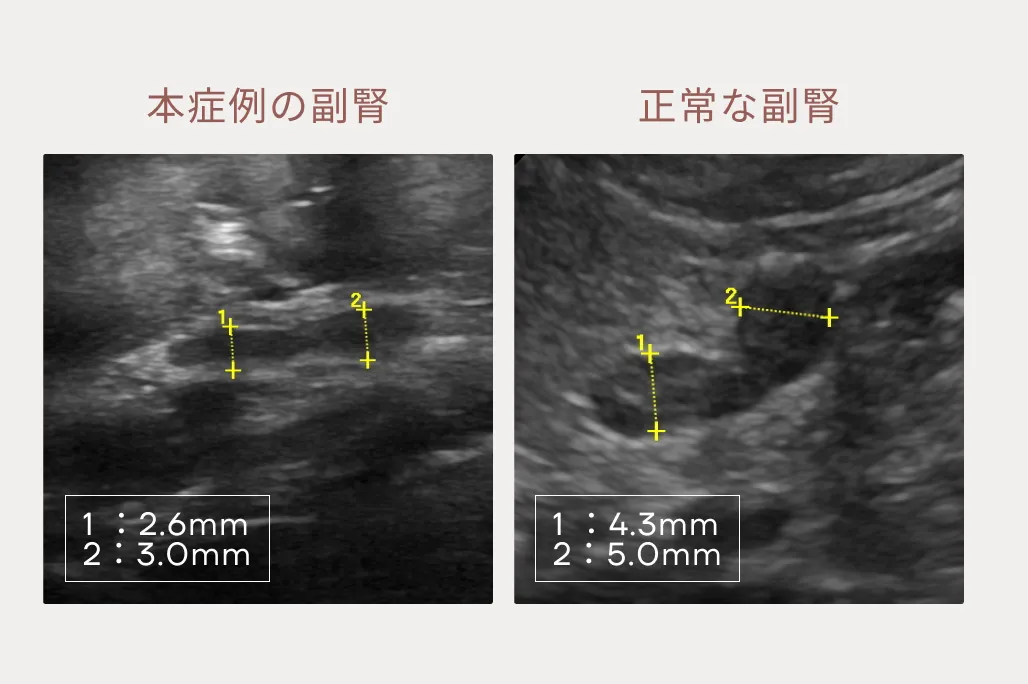

異物・アジソン病・びまん性胃腸疾患(慢性胃腸炎、リンパ管拡張症、リンパ腫)・ガストリノーマなどを鑑別疾患として念頭に入れ検査を行いました。身体検査と一般血液検査では何も異常がありません。エコー検査では胃の運動性低下、小腸の粘膜面は軽度に不整でやや腸管の腫れもみられます。特に気になったのは副腎が小さいことです。(図1・2)異物を疑う所見がないため、次にホルモン検査を行うと低値を示し、ホルモン分泌不足が認められ、「非定型アジソン病」と診断しました。